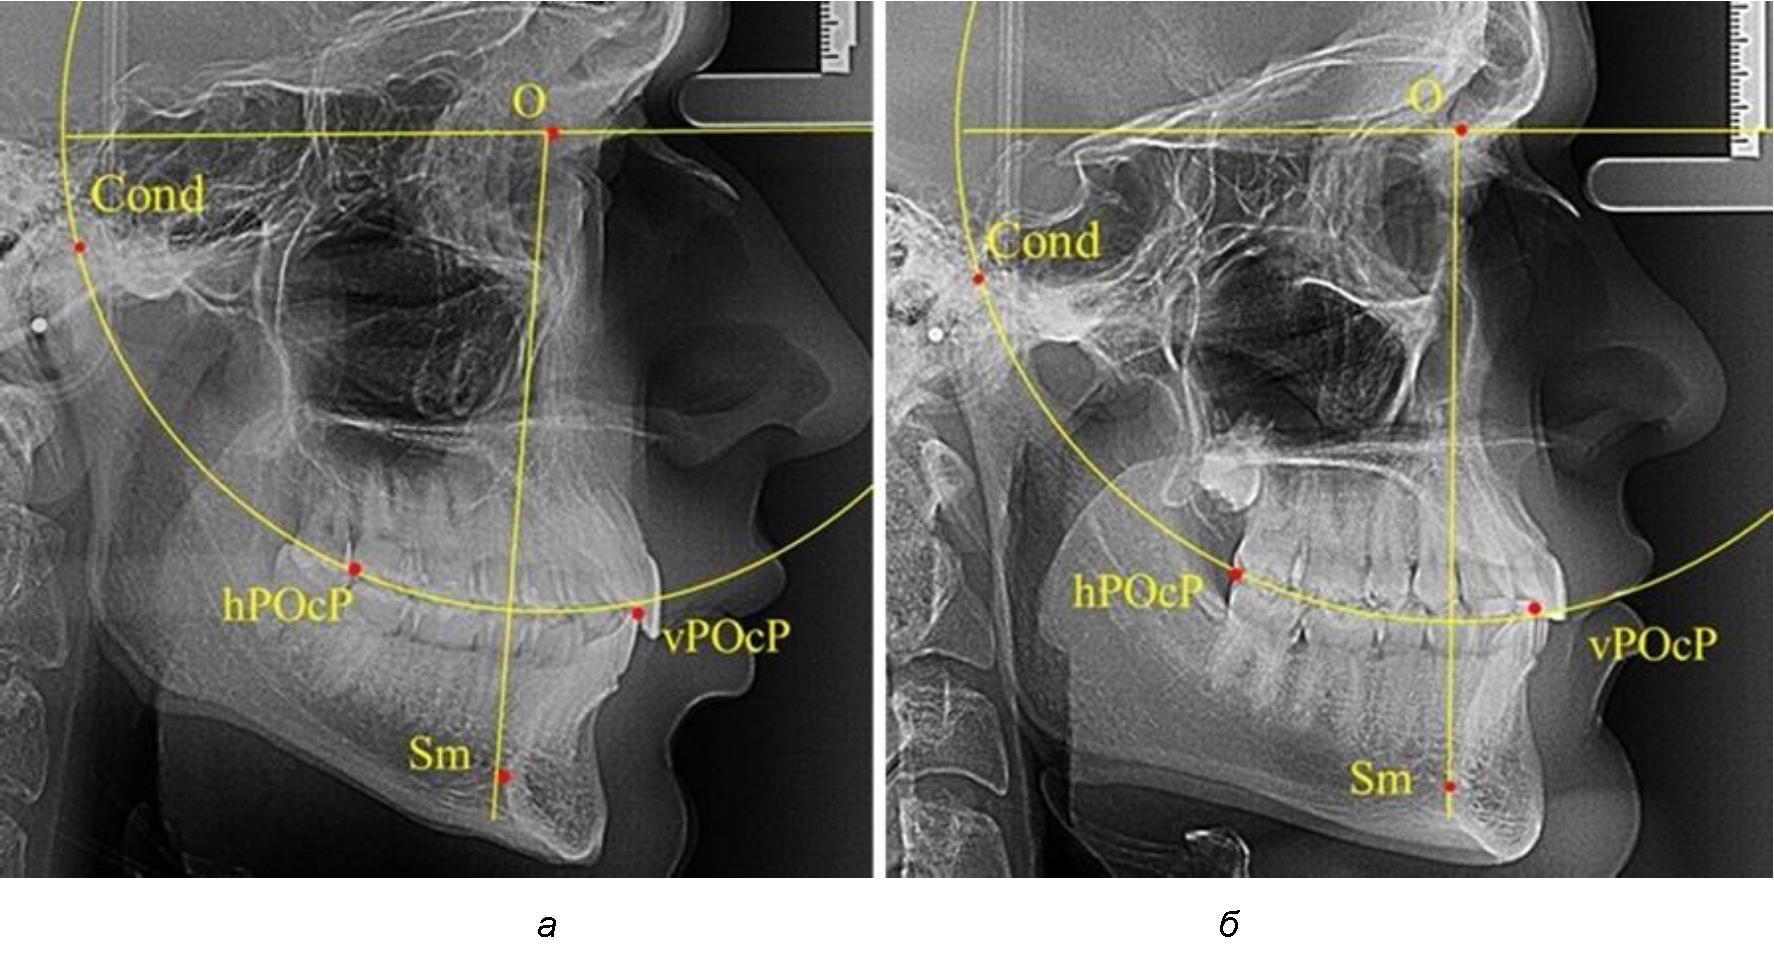

В группе рентгенограмм, выделенных по признаку протрузионного положения резцов, также проводилось распределение на подгруппы с учетом широтных размеров подбородочного выступа.

Анализ результатов показал, что практически при всех вариантах подбородочного выступа в данной группе исследования первые премоляры, как правило, располагались впереди стресс-оси Bimler. Рентгенограммы пациентов с протрузионным положением резцов при среднем и узком варианте подбородочного выступа представлены на рис. 3.

Таким образом, для людей с протрузионным типом зубочелюстных дуг характерно расположение первых премоляров впереди стресс-оси, и этот показатель не может быть использован в качестве выбора метода лечения аномалий для данной группы исследования вне зависимости от формы подбородочного выступа.

Рис. 3. Положение первых верхних премоляров при протрузии со средними (а) и узкими (б) размерами подбородка